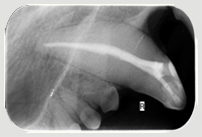

In der Kleintier-Ordination Mittertreffling wird eine moderne digitale Entwicklung verwendet, die die Strahlenbelastung für Ihr Tier verringert. Ohne Zahnröntgen wird das Ausmaß des Knochenverlustes oft unterschätzt und bei der Katze viele Zahnresorptionen übersehen oder unterschätzt. Zudem ist bei einer wie in der Tier-Zahnheilkunde in einer Sitzung durchgeführten Wurzelbehandlung (Endodontie) eine Kontrolle durch Zahnröntgen unbedingt notwendig. Selbst Tumoren können sehr gut erkannt werden und auch die Kontrolle einer Zahnbewegung (Orthodontie) sollte durch Zahnröntgen erfolgen.

Eckzahn Fraktur Eckzahn mit Feile Eckzahn nach Wurzelbehandlung

Zahnröntgen Oberkiefer Hund P4 Zahnröntgen Unterkiefer Hund normal Zahnröntgen Oberkiefer Hund dreiwurzliger P3